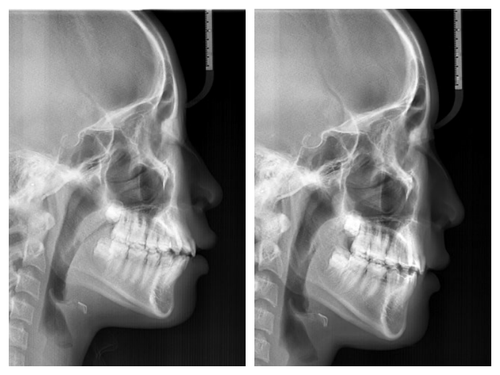

사실 골격적인 비대칭이 심해서 교정이 끝나도 비대칭이 남겠지만 돌출이 개선되면 훨씬 예뻐질것이기에 과감히 발치를 하고 좌,우 최대한 중심선을 맞추면서 교정을 끝낸 케이스

입이 들어가서 예뻐진 것 뿐아니라 사진을 찍으면 두드러지던 비대칭도 많이 줄어들었다.

네 개의 소구치를 발치하고 교정을 시작했다.

돌출입 교정을 통해 입술의 모습이 많이 바뀌니 잇몸 노출량도 훨씬 줄어서 웃을때 신경이 더 쓰인다고...